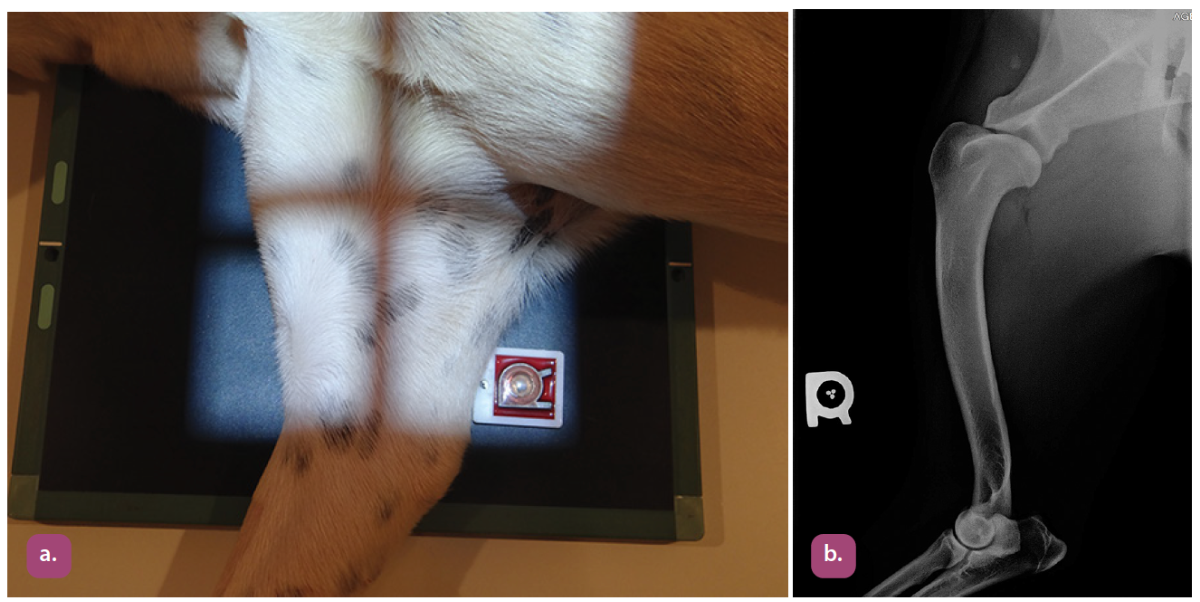

mediolateral projection of the femur

Craniocaudal projection of the femur